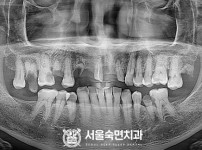

임플란트-전후사진3

치과를-선택할-때-꼭-확인하세요-서울숙면치과-임플란트-전후사진